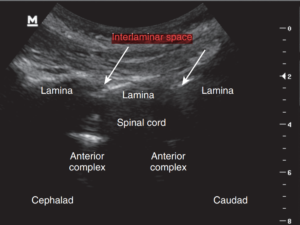

نخاع در تمام طول ستون فقرات، در داخل مهرهها و توسط سه لایه محافظ احاطه شده است.

خارجیترین لایه، دورا (Dura) نام دارد.

به فضای بین این لایه و سطح داخلی مهرههای ستون فقرات، فضای اپیدورال گفته میشود که با بافت چربی و عروق کوچک پر شده است.

در تصاویر زیر، این فضا با هایلایت سبز مشخص شده است.

به دلیل نزدیکی فضای اپیدورال به نخاع، میتوان برای بلاک اعصاب نخاعی (اعصابی که مستقیماً از نخاع خارج میشوند) داروهای بیحسی را به داخل این فضا تزریق کرد.